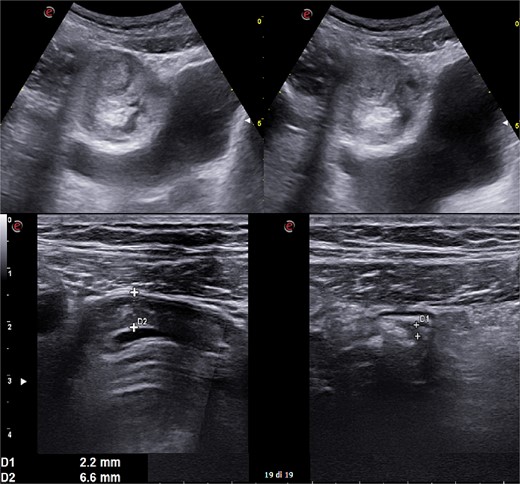

A 31-year-old male was complaining episodes of abdominal pain in the umbilical region with nausea. In medical history he underwent an appendectomy. Chronic gastritis was found on esophagogastroduodenoscopy (EGD) and proton-pump inhibitors (PPI) treatment was started, with regression of symptoms. After two months, he took ketoprofen for back pain for two days when a severe abdominal pain in the umbilical and right iliac region started, with nausea and vomit. He had normal vital signs and tenderness in the right lumbar and iliac regions. Blood exams showed leucocytosis (GB 14.120 × 106/ml) with neutrophilia (88%). A plain abdomen X-ray showed absence of representation in the right regions, with small bowel loops’ distension on the left (Fig. 1). An abdomen US displayed the presence of visceral distension with cockade appearance, consistent with an inflammatory condition of the cecum and the ileocecal site, with wall thickening of 6 up to 10 mm and free fluid near the cecum (Fig. 2). Contrast-enhanced CT confirmed wall thickening of the last ileal loop and the cecum up to 20 mm (Fig. 3A and B). Antibiotic therapy was started. The next day the pain worsened and there was an abdominal mass in the right iliac region with rebound tenderness. Blood examination showed further increase in leucocytosis (GB 18560) and a new CT was done. The wall thickening increased up to 24 mm, and the last ileal loop was more hypointense, with a twisted appearance around its mesentery (Fig. 3C). Exploratory laparotomy was performed. During surgery we found an ileal intussusception of the distal ileum near the cecum, and an ileocecal resection with ileo-colic anastomosis was done. On the first post-operatory day he developed haematochezia and acute anaemia, so he underwent reintervention with resection of the anastomosis and ileostomy. The following post-operative course was uneventful.

Abdomen ultrasound image displaying visceral distension with a cockade appearance consistent with an inflammatory condition of the cecum and the ileocecal site, showing wall thickening of 6 up to 10 mm and free fluid near the cecum.